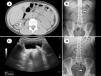

A total of 5909 lithotripsies were performed during the study period, out of which 1% corresponded to patients under 18 years (n=59): median age, 7 years (range, 1–17), 50% female (n=30). The average size of the stones was 1cm (range, 0,8–4). Seventy-eight percent of patients had a single stone (n=46), 10% had 2 (n=6) and 12% had 3 or more (n=7). In 36 patients (61%) the stones were located in the kidney, in 20 (33%) they were in the ureter, in 2 they were in the bladder, and a single patient had nephroureterolithiasis (Fig. 2). The mean duration of treatment was 45minutes (SD, 18), the mean number of shock waves 2135, the mean maximum wave intensity 8kV (SD, 3) and the mean duration of fluoroscopy was 4.2minutes (SD, 3). The mean radiation dose was 11Gy/cm2 (SD, 10.5). Kidney stone analysis was only performed in 11 of the patients, showing that the calculi were most frequently made of calcium oxalate+calcium phosphate (3/11) or calcium oxalate (3/11), followed by calcium phosphate (2/11), apatite+calcium phosphate (2/11) and cystine (1/11). Fifteen patients required repeated treatment (25%): 9/15 one additional session (60%), 4/15 two sessions and 2/15 four sessions (13%) due to early recurrence. The incidence of complications following ESWL was 10% (n=6/59), in 4 cases it was abdominal pain, which required admission for analgesia in only one of the patients, and in the other 2 cases the complications were fever with leukocyturia with a negative urine culture. There were no cases of steinstrasse post ESWL. Since the treatment was provided in a referral hospital, many patients were followed up in other centres, so we lost 21 of the 59 children to follow-up (35.5%). In the 38 cases that we were able to follow-up, the success rate (success defined as absence of lithiasis or residual stones < 3mm) was 84% (n=32) at 12 months post treatment. In these patients, we conducted a stratified analysis of the success rate by age group: 0–6 years (n=15) 93% 6.1–12 years (n=11) 72% and 12.1–18 years (n=12) 83%, with no statistically significant difference (P=.109). There were also no statistically significant differences between age groups in the size or location of the stones (P=.083 and P=.231, respectively); although ESWL was more effective in children with nephrolithiasis aged 0–6 years (100%) compared to those aged 6–12 years (57%) or 12–18 years (80%).